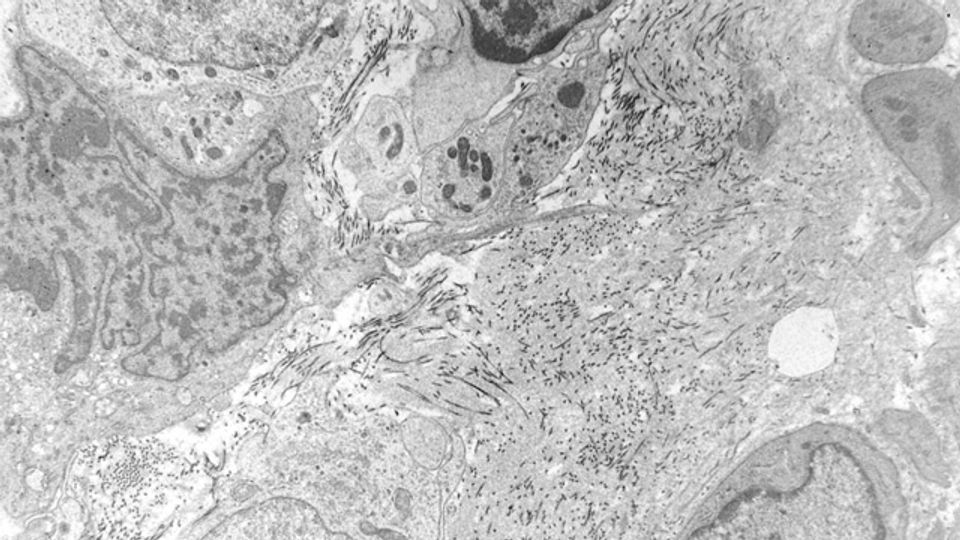

Soft tissue sarcoma photographed through an electron microscope. Credit: Dr. Timothy Triche/ National Cancer Institute

Soft-tissue sarcoma is a rare type of cancer that forms in the muscle, fat, blood vessels, nerves, tendons and joint lining. It most commonly occurs in the arms, legs and abdomen, and kills more than 5,000 people in the U.S. each year, according to the American Cancer Society.